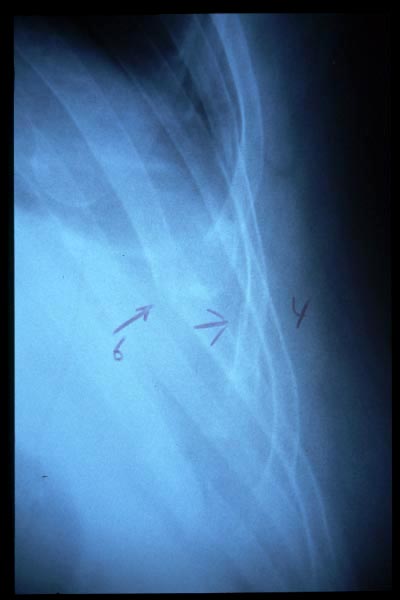

Fractura costal

Fractura costal por caída.

Paquipleuritis. Fractura costal.